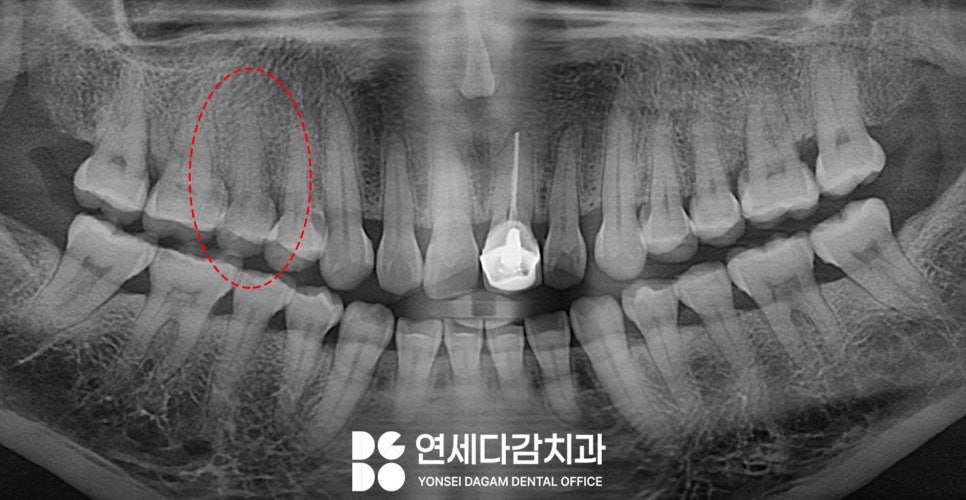

문제는 균열이 미세할 경우

엑스레이에서도

잘 보이지 않는다는 점입니다.

송파역 치과 에서 교합 검사와

타진 검사를 함께 시행하는 이유도

이렇게 눈에 보이지 않는 손상을 찾기 위함입니다.

근관치료 과정에서 치아 내부에서도

송파역 치과 에서 표시한 것처럼

균열선이 발견된 것을 볼 수 있습니다.